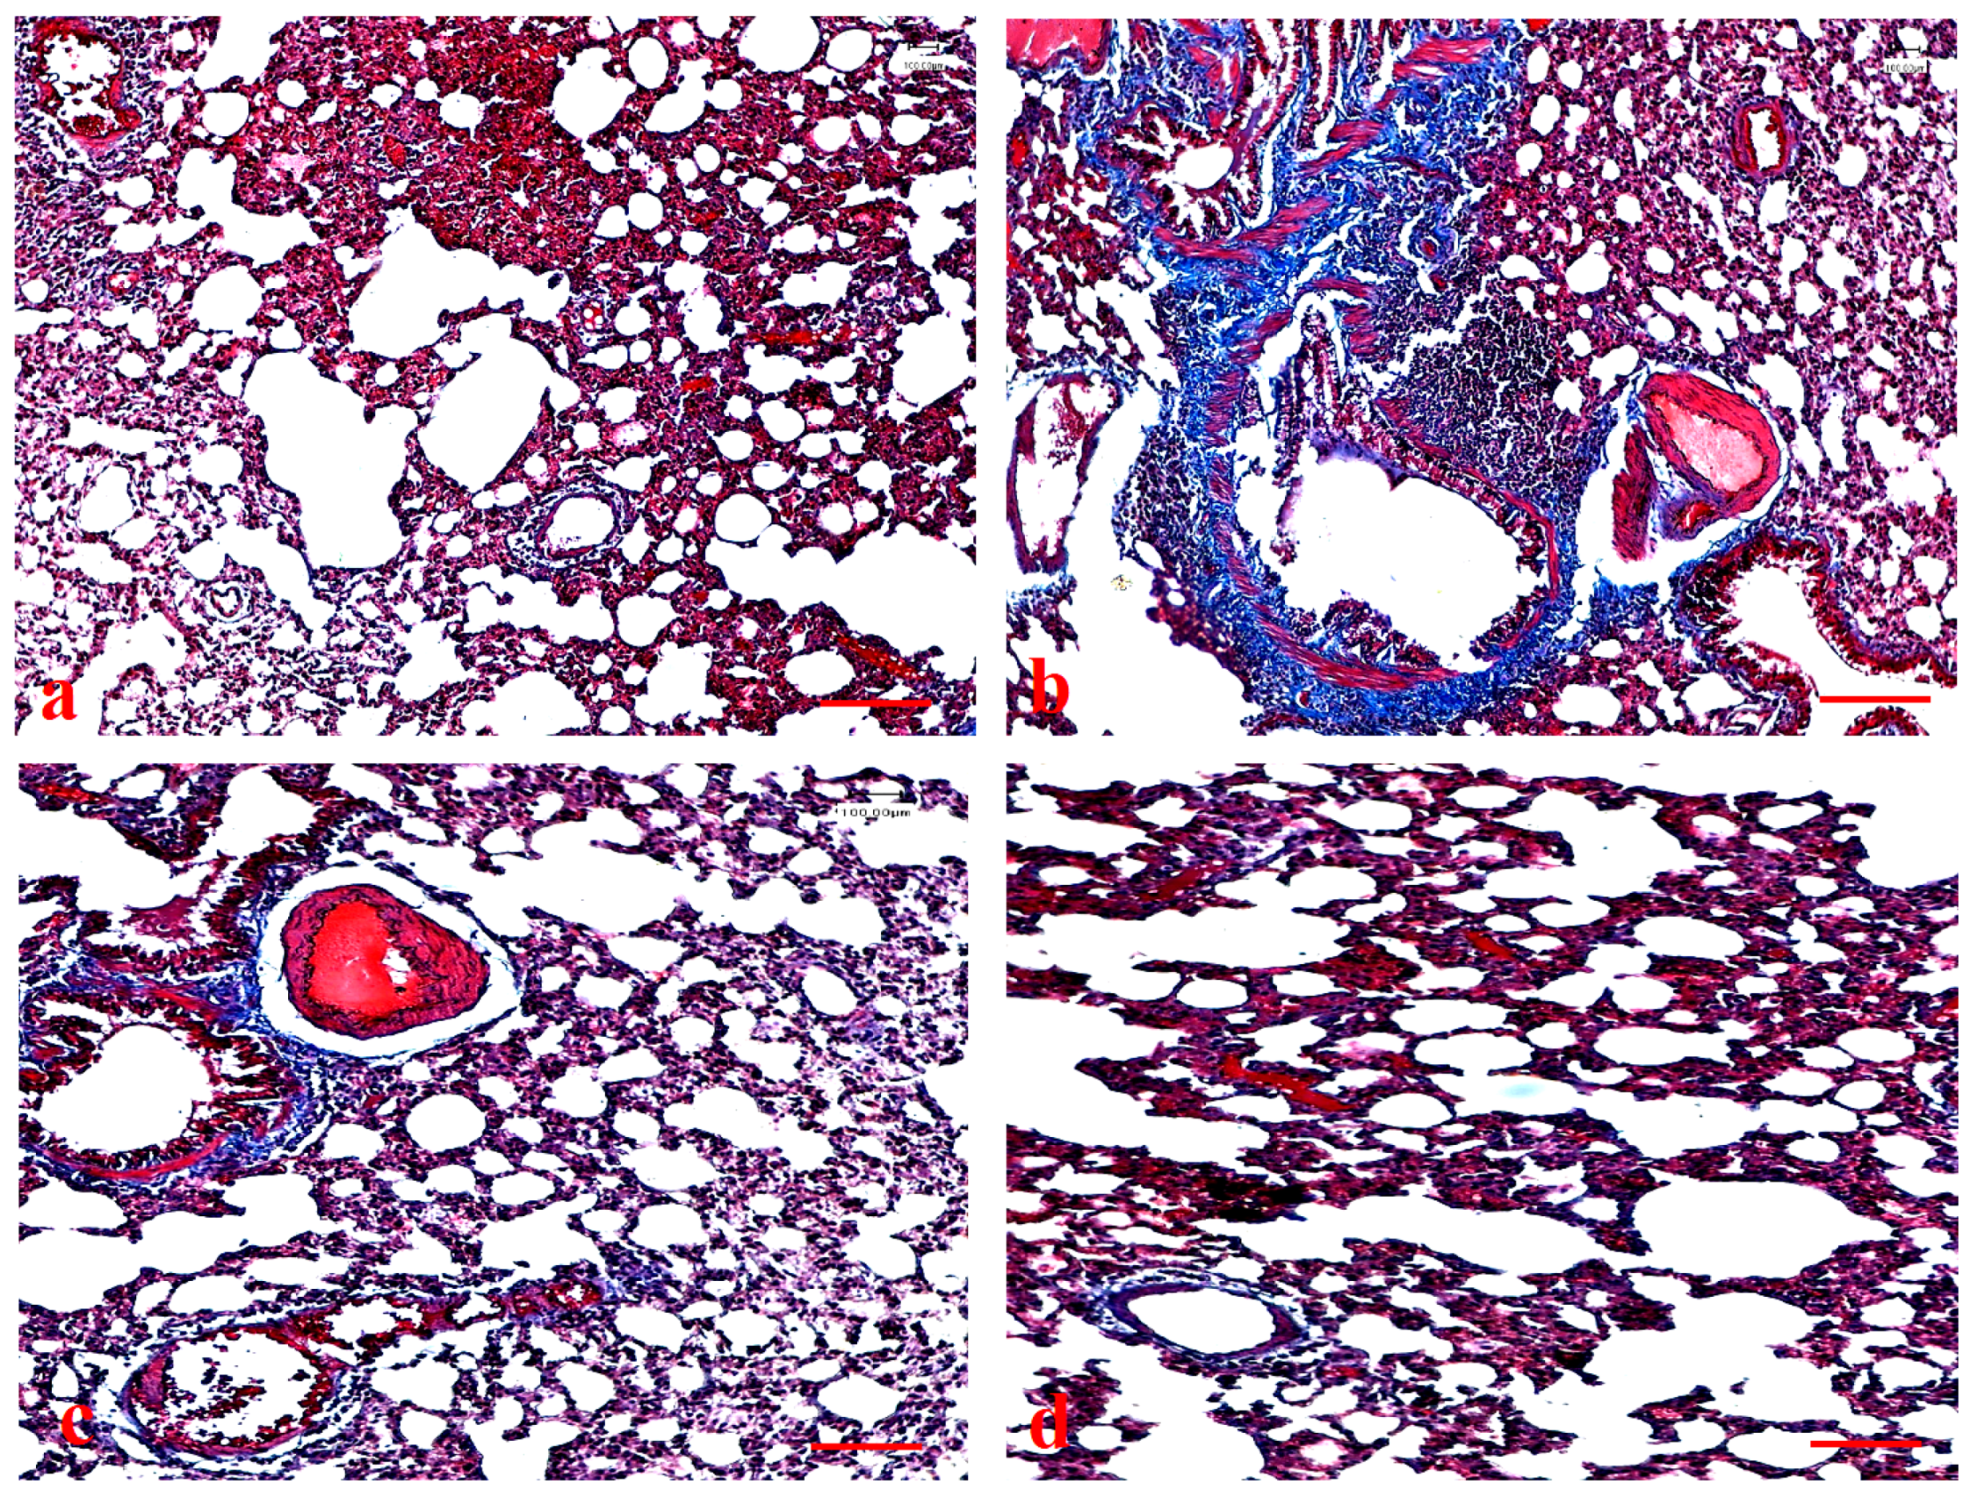

3.9. Effects of Ajwa Date Extract on Lung Fibrosis Caused by B(a)P in Rats

3.10. Effects of ADE on Expression Pattern of Bax and VEGF Protein in Lung Tissue